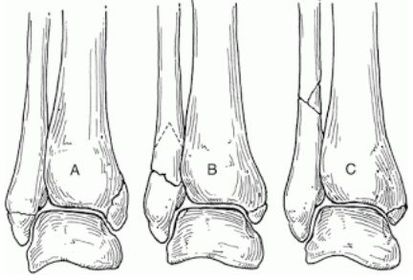

| What classification system is this? Describe the 3 classifications | Weber Ankle Fracture Classification A = Fracture below syndesmosis B = Fracture begins at joint level & extends proximally in an oblique fashion C = Fracture above the joint line |